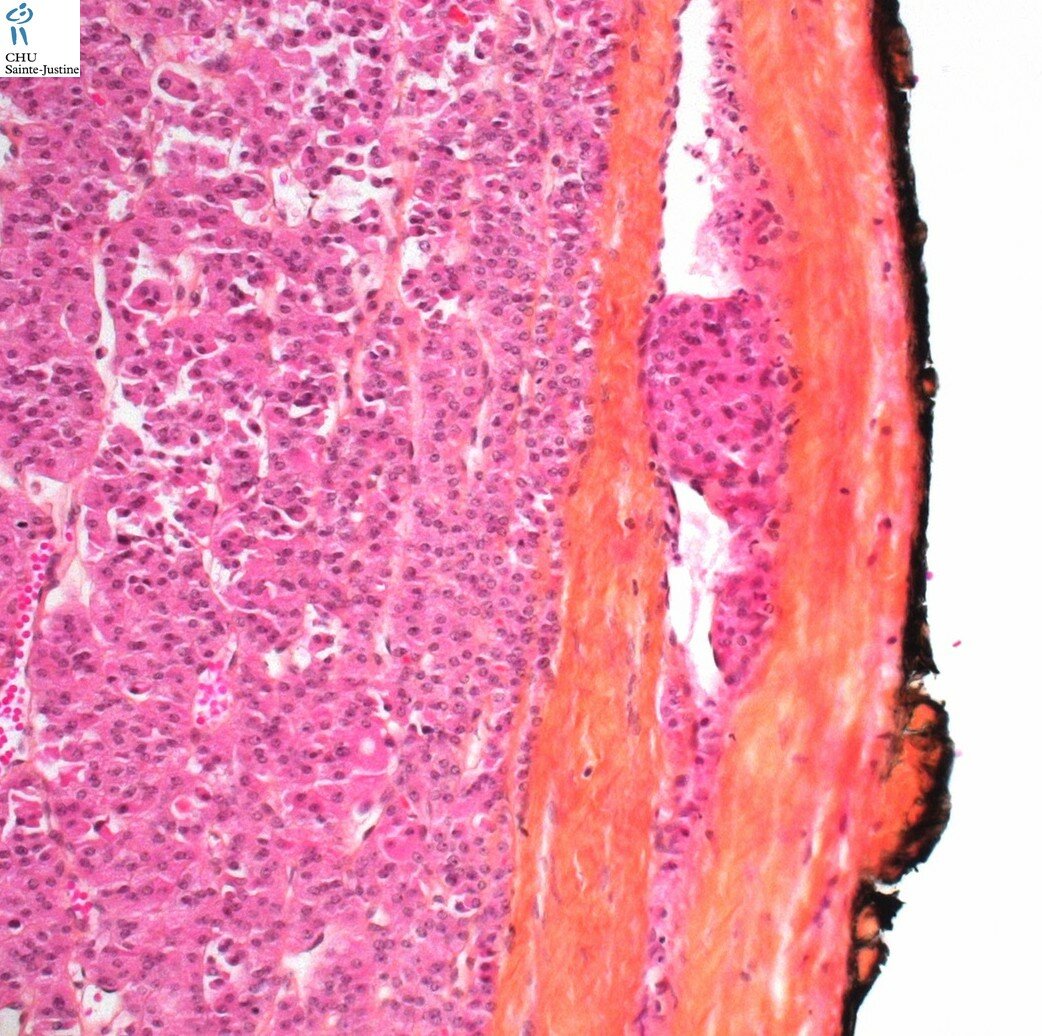

thyroid oncocytic tumors

thyroid oncocytic tumor, Hurthle cell neoplasms of the thyroid

thyroid oncocytic adenoma

thyroid oncocytic carcinoma